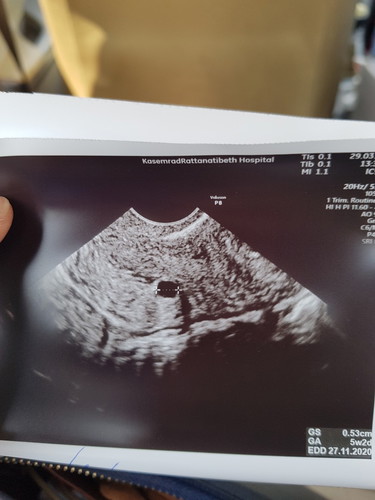

ครั้งที่แล้ววันที่19/3 เราไปหาหมอ แต่หมอซาวให้แต่ไม่เห็นอะไรเลยค่ะ วันนี้ไปอีกพบถุงการตั้งครรภ์ค่ะ ดีใจมาก แต่ก็แอบกลัว อยากถามแม่ๆว่า จะเห็นน้องได้ตอนไหนค่ะ